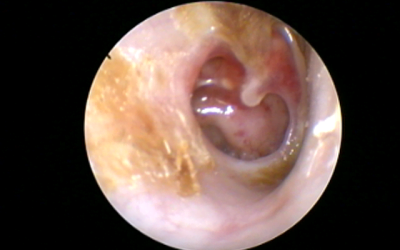

From Need for Hearing Aids to Almost Normal Hearing

This 30 plus patient had history of failed ear surgeries in the past and had come with lots of hopeHe had a huge ear drum perforation and was advised hearing aids, felt depressed and came for an opinion. I advised Cartilage Tympanoplasty and the results speak. ...